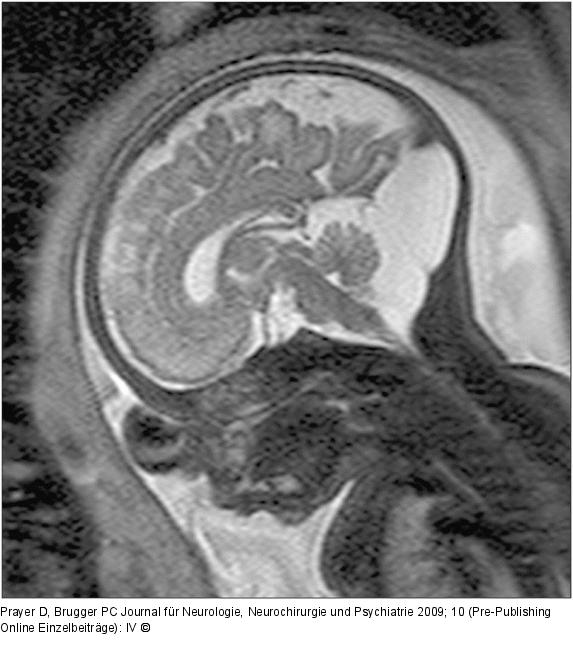

Abbildung 3: Fetus - 33. SSW

33. SSW. In dieser sagittalen Schnittführung erkennt man einen hochstehenden Torculus Herophili, eine große hintere Schädelgrube, die von einer zerebellären Falz durchzogen wird, sowie einen sonst unauffälligen Inhalt der hinteren Schädelgrube, wobei insbesondere kein Hinweis auf eine Gewebekompression besteht. Auch supratentoriell regelrechte Verhältnisse. Die Diagnose lautet daher Megacisterna magna. Neurologische Symptome sind hier nicht zu erwarten. |